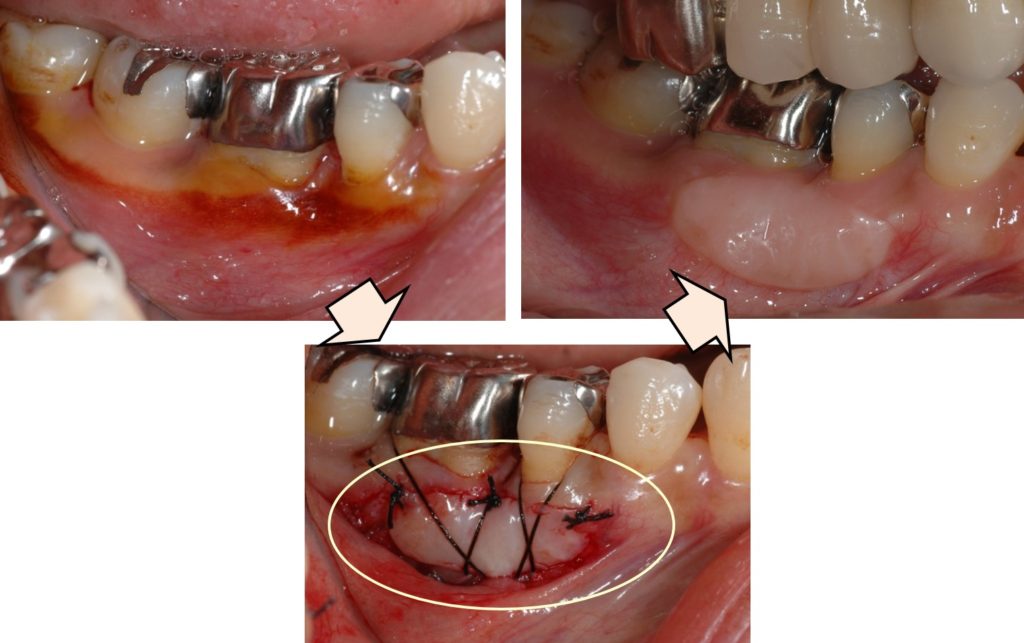

術前写真は金属冠の周りに「動く歯茎」しかないため、患者さん自身によるブラッシングが困難であったため、「動かない歯茎」を口蓋から移植しています。

これにより歯の周囲の歯茎は動かなくなり、ブラッシングが容易になります。